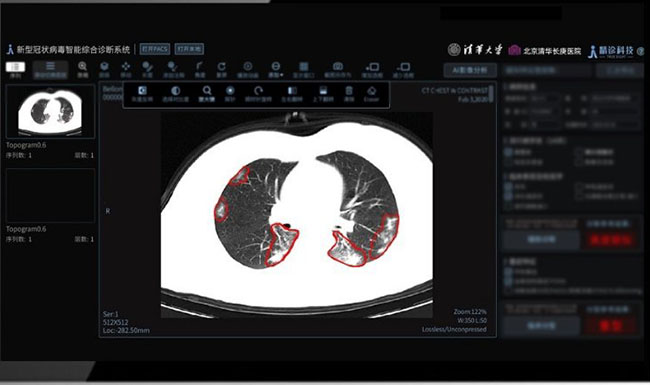

Tsinghua has also released the Smart Diagnosis System equipped with three key functions -- smart image diagnosis, clinical diagnosis, and clinical classification.

It is capable of processing a large number of chest CT images of suspected cases and coming up with comprehensive clinical diagnoses in accordance with the most up to date government guidelines within a very short timeframe. It serves to significantly cut the workloads for clinicians and radiologists and shortens waiting periods for patients.

The project team has utilized clinical records of COVID-19 patients in Wuhan for big-data analysis and used AI deep learning to identify the characteristic patterns in CT images, thus enabling the system to detect and identify COVID-19 infections.

Furthermore, in line with the fifth edition Guideline of Prevention and Treatment of the Novel Coronavirus (2019-nCoV) Pneumonia released by the government, a smart diagnosis module was designed that combines comprehensive input of imaging and epidemiological details, symptoms, and other key clinical information in case investigation.

Capitalizing on smart interpretation of respiratory function parameters, it offers an adaptable clinic classification module that classifies patients by severity of infection. These three modules have been integrated to comprehensively enable clinic and image-related functions.